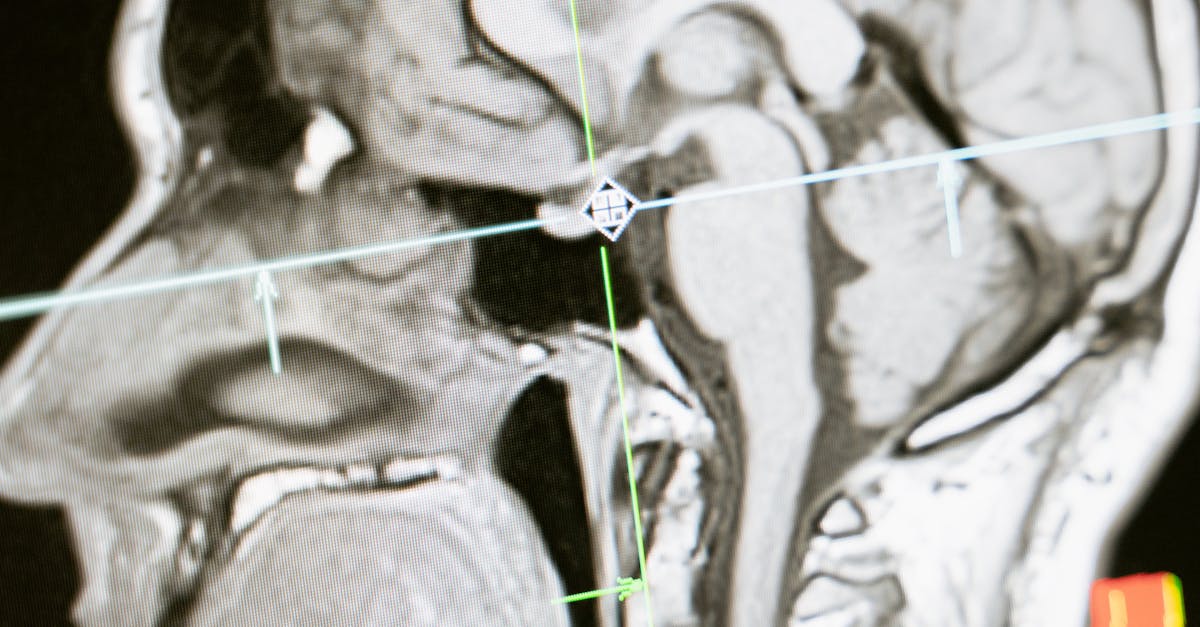

Brain imaging has advanced enough to map activity in real time. Tools like fMRI track blood flow to active areas, giving a clear picture of what's happening during recall. This study built on that to probe deeper. It comes at a time when memory loss in aging populations is a growing concern, with millions affected by conditions like Alzheimer's worldwide.

During scans, the machine measured blood flow changes. Active brain spots get more oxygen-rich blood, which fMRI detects. The images showed 3D maps of activity. To everyone's surprise, the patterns looked almost the same for both tasks.